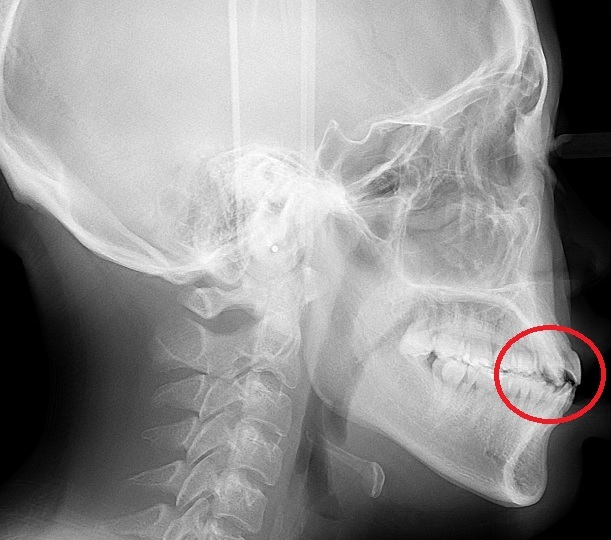

在最後進行X光拍攝後,牙套建膜的前置流程也正式進入尾聲,諮詢護士為了提供更私密的矯正諮詢,特別在諮詢室內將各個不同類型牙套矯正方式向我做了仔細說明,而現在有不少人礙於外表,都會選擇隱形牙套來做牙齒矯正,這一點即使是我妹也是一樣。